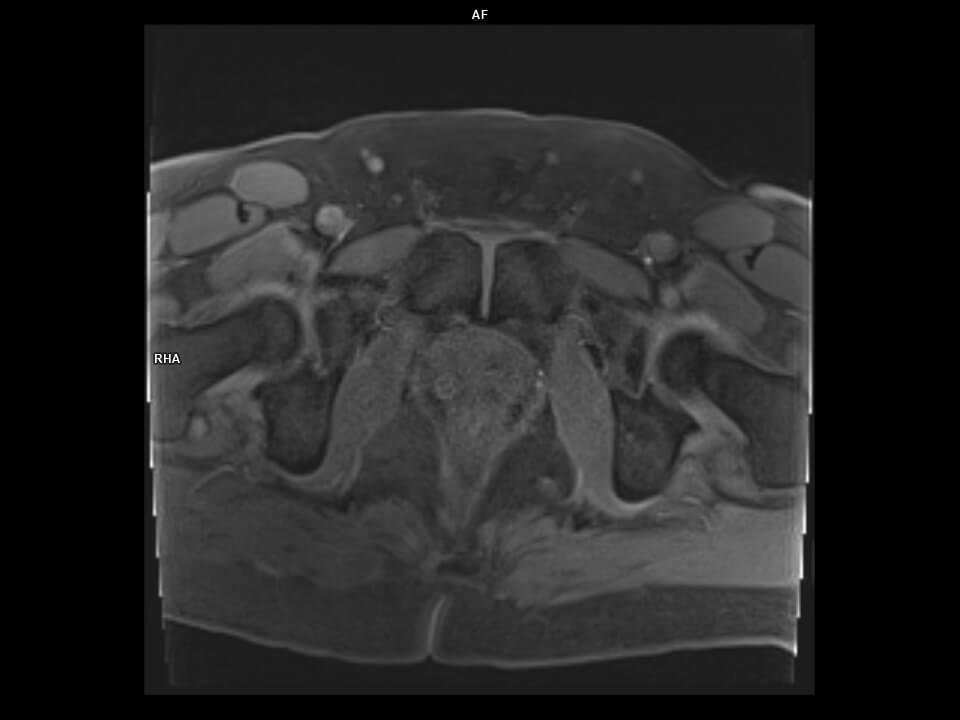

AXIAL GRASPVIBE DYNAMIC-MAGNETOM Vida

AXIAL GRASPVIBE DYNAMIC-Vida/BODY 18 / SPINE 48/Resolution-320/Scan Time-5.6 second/Aceleration-CS